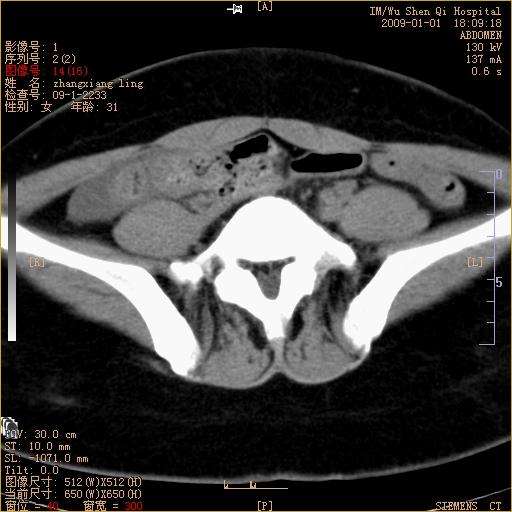

标题: CT17527:F31Y,腹痛伴血便9小时 [打印本页]

标题: CT17527:F31Y,腹痛伴血便9小时

升结肠肠壁不规则增厚,肠腔狭窄,考虑升结肠占位,建议增强扫描

升结肠肠壁不规则增厚,肠腔狭窄,考虑升结肠占位,建议增强扫描,不除外肠套叠.

升结肠肠壁不规则增厚,似呈同心圆改变,其有积液。结合病史首先考虑肠套叠伴肠壁坏死可能性大,结肠肿瘤待排。

患者已手术,结果肠系膜血栓形成肠坏死

结果:患者已手术,结果肠系膜血栓形成肠坏死。回过头再看局部肠壁增厚有分层(高密度坏死及低密度水肿)表现。